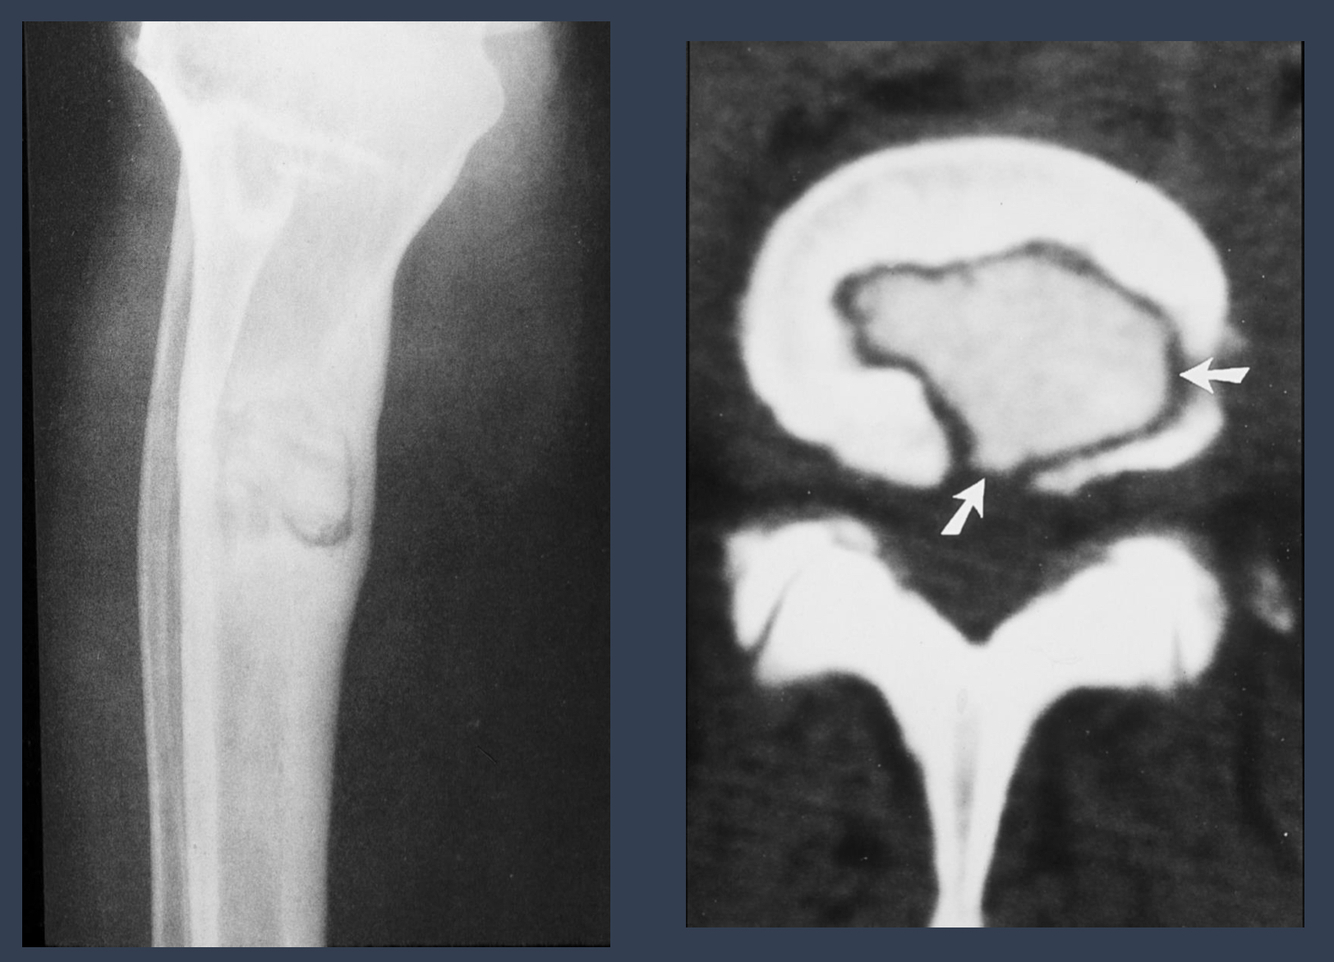

what is this condition?

oseomyelitis

what are the arrows pointing to?

sequestrum = island of dead bone

what is noteable in the long bone?

involucrum = thick layer of periosteal new bone that forms around sequestrom

what is the opening from the bone to the skin called that may show up in this patient?

cloaca = opening in an involucrum that drains pus and debris out of infected bone

via sinus tract